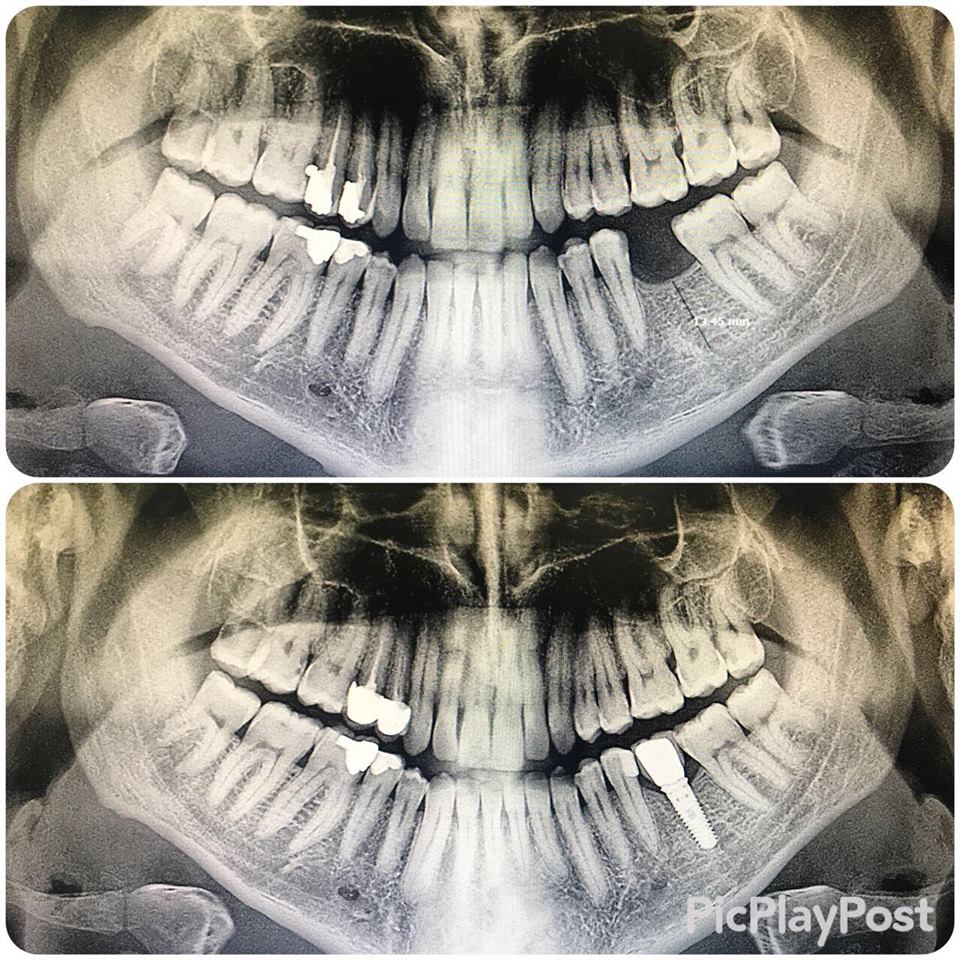

İMPLANT TEDAVİSİ

implant tedavisi